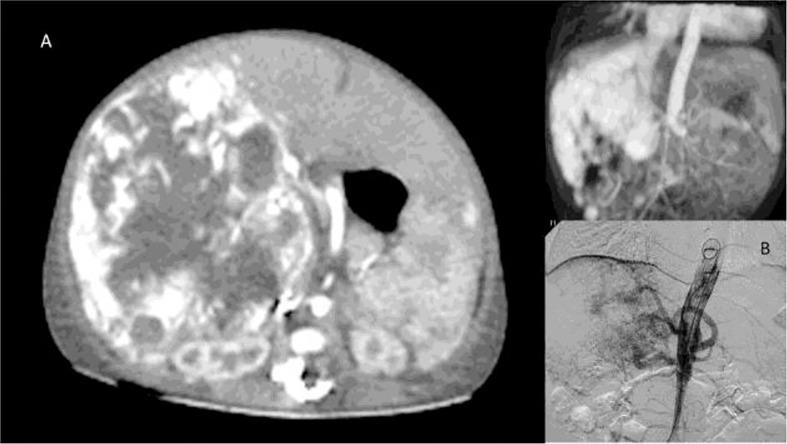

The role of liver transplantation in the care of primary hepatic vascular tumours in children.

Liver transplantation (LT) is the standard of care for many liver conditions, such as end-stage liver diseases, inherited metabolic disorders, and primary liver malignancies. In the latter group, indications of LT for hepatoblastoma and hepatocellular carcinoma evolved and are currently available for many non-resectable cases. However, selection criteria apply, as the absence of active metastases. Evidence of good long-term outcomes has validated the LT approach for managing these malignancies in the context of specialist and multidisciplinary approach. Nevertheless, LT's role in treating primary vascular tumours of the liver in children, both benign and malignant, remains somewhat controversial. The rarity of the different diseases and the heterogeneity of pathological definitions contribute to the controversy and make evaluating the benefit/risk ratio and outcomes quite difficult. In this narrative review, we give an overview of primary vascular tumours of the liver in children, the possible indications and the outcomes of LT.